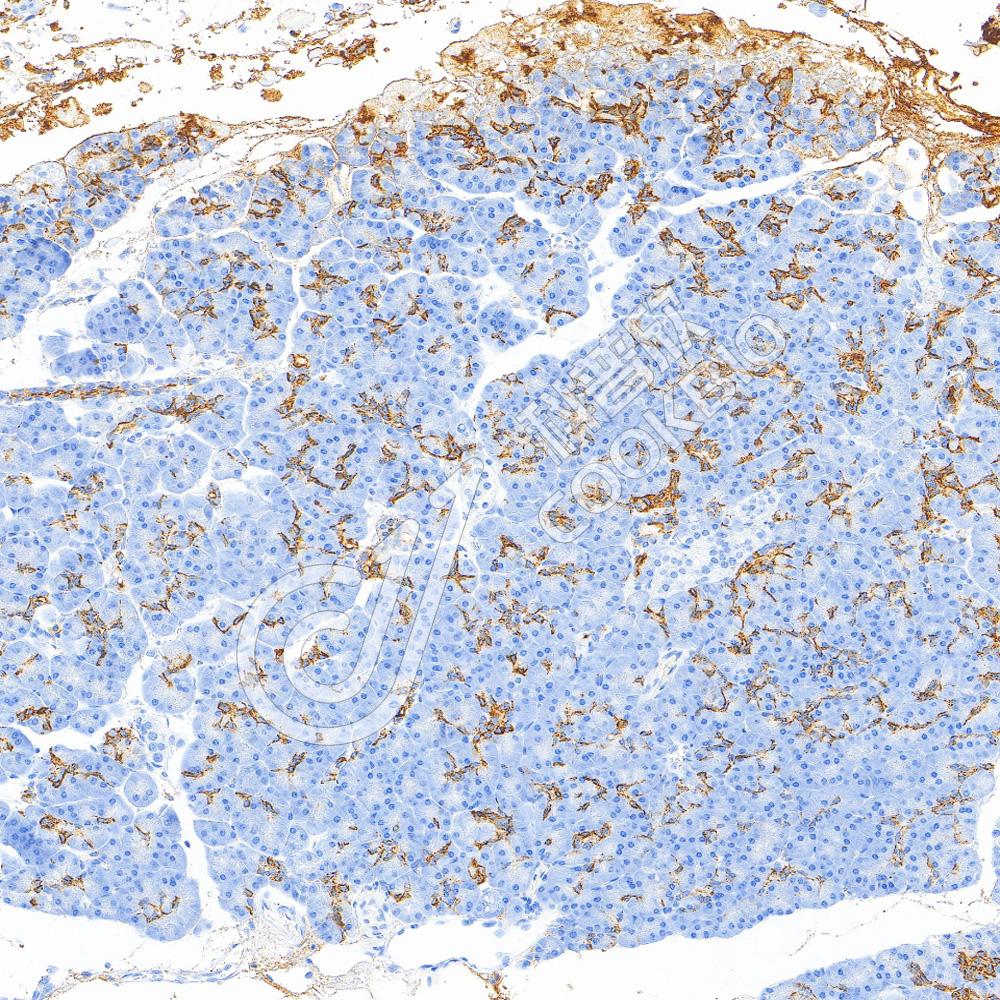

IHC检测CA19-9蛋白(货号 K5450375).

样品: 人结肠癌, 4%多聚甲醛 (货号KSG1101) 固定12-24小时.

抗原修复: Tris-EDTA抗原修复液(pH 9.0) (KSG1203), 100℃, 25分钟.

—抗: 1: 500稀释, 4℃ 孵育过夜.

二抗: S-vision免疫组化多聚二抗(山羊抗小鼠), 即用型(货号KB3903), 室温孵育20分钟.

样品: 人胰腺, 4%多聚甲醛 (货号KSG1101) 固定12-24小时.